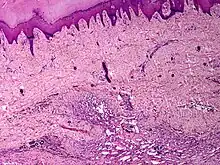

Angiomatosis is a non-neoplastic condition[1] characterised by nests of proliferating capillaries arranged in a lobular pattern, displacing adjacent muscle and fat.[2] It consists of many angiomas.[3]

It is a vascular malformation wherein blood vessels proliferate along with accompanying mature fat and fibrous tissue, lymphatics and sometimes nerves.[2] They may involve skin, subcutaneous tissue, skeletal muscle and occasionally bone.[2]